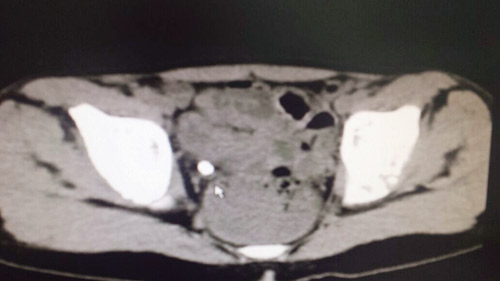

تمكن الفريق الطبي لقسم جراحة المسالك البولية بالمستشفى السعودي الألماني بالرياض من استخراج حصوة كبيرة من الحالب الأيمن لطفل يبلغ من العمر ست سنوات، باستخدام المنظار والليزر دون جراحة. وكان الطفل صاحب السنوات الست يعاني من نوبات عديدة ومتكررة وشديدة لمغص كلوي حاد في الجانب الأيمن مع بول مدمم... وبإجراء الفحوصات الطبية اللازمة تبيَّن وجود حصوة كبيرة في الحالب الأيمن... وتم إجراء عملية تفتيت للحصى بالليزر واستخراجها عن طريق المنظار دون جراحة في قسم جراحة المسالك البولية. وخرج الطفل -بحمد الله تعالى- من المستشفى السعودي الألماني بالرياض بعد يوم واحد من إجراء العملية بحالة صحية ممتازة وينعم بالصحة والعافية بفضل الله تعالى وتوفيقه. ومن الجدير بالذكر أن نسبة الإصابة بحصوات المسالك البولية قد ارتفعت خلال العقدين الماضيين. ومن أهم وسائل الوقاية من الحصوات في المسالك البولية هي المحافظة على شرب السوائل بنسبة كبيرة ومنتظمة بما لا يقل عن لترين في اليوم، وكذلك التقليل من اللحوم الحمراء والأملاح وخصوصًا الوجبات السريعة.